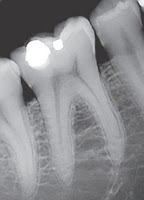

En la figura encontrarán diferentes elementos relacionados con la toma de radiografías, por favor identifiquelos colocando la letra y el nombre del elemento.